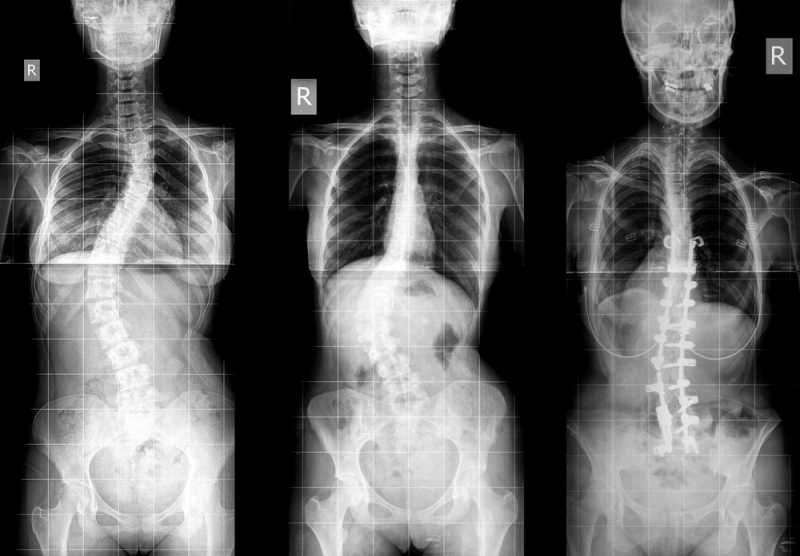

В лечении и профилактике сколиоза, несмотря на давнюю историю этого заболевания, остается множество проблем. Одна из них заключается в том, что как-то воздействовать на развитие заболевания нехирургическими методами можно только примерно до 17–19 лет. Именно на этих годах жизни окончательно формируется опорно-двигательный аппарат. При этом необходимо отслеживать прогресс болезни в динамике, чтобы адекватно назначать лечение, то есть нужны удобные инструменты мониторинга болезни, которые помогут врачу. Здесь важно еще и то, что далеко не все обращаются за медицинской помощью вовремя, а зачастую уже тогда, когда необходимо проводить операцию. А хирургическое вмешательство – это всегда крайняя и небезопасная мера лечения. До сих пор врачам очень сложно определить причину сколиоза, а также «очаги» заболевания, на которые нужно воздействовать в ходе лечения. Из-за этого приходится проводить очень много медицинских исследований типа рентгена, МРТ, при этом не всегда их результаты интерпретируются верно, отметил научный сотрудник кафедры нанофотоники и метаматериалов Юрий Балошин. Он проводит исследования по разработке физико-математической модели ОДА совместно с заведующим кафедрой высшей математики Игорем Поповым, группой обучающихся на этой кафедре, а также со специалистами центра «Огонек».

«В уже имеющихся физико-математических моделях сколиоза есть один существенный недостаток: в их основе лежит математический анализ баз данных, полученных при клинико-рентгенологической диагностике. Но ни в одной из этих моделей сколиоз не описывается как динамический процесс. С точки зрения классической биомеханики здоровый позвоночный комплекс рассматривается как двухколонное образование, состоящее из несущей колонны (позвонки и межпозвонковые диски) и функциональной (позвонковые дужки, остистые и поперечные отростки, межпозвонковые суставы). Первая, несущая колонна поддерживает положение и вес всех органов и систем в туловище, а вторая, функциональная, обеспечивает движение в позвоночном комплексе. Для нормального состояния позвоночного столба необходимо вертикальное положение колонн; верхние и нижние концы колонн должны быть на одном уровне, а расстояние между колоннами на любом уровне должно оставаться постоянным. Мы предлагаем математическое описание образования деформаций по всем этим трем плоскостям в двухколонной системе, приближенной к реальному позвоночному столбу человека», – прокомментировал Юрий Балошин.